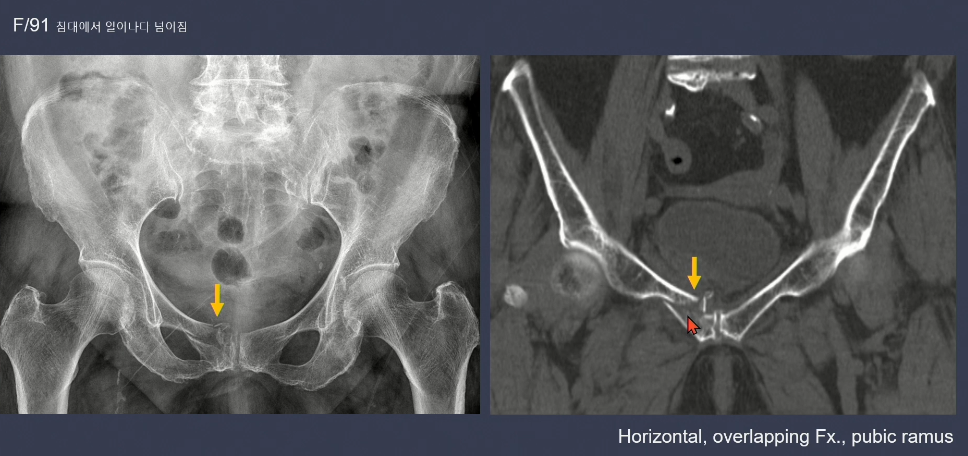

3. LC type